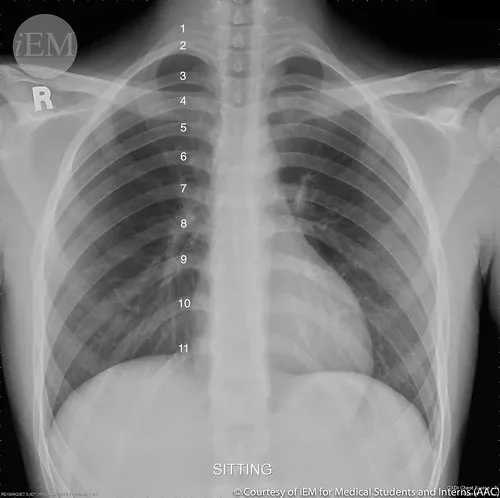

My son Brock was recently diagnosed with a very rare form of lung cancer. He’s only 28 and has never been a smoker, so as you can imagine, this news has come as a huge shock to him, and our entire family. Brock is currently receiving care in Minneapolis and will also be traveling to MD Anderson in March to ensure he gets the best possible treatment and outcome.